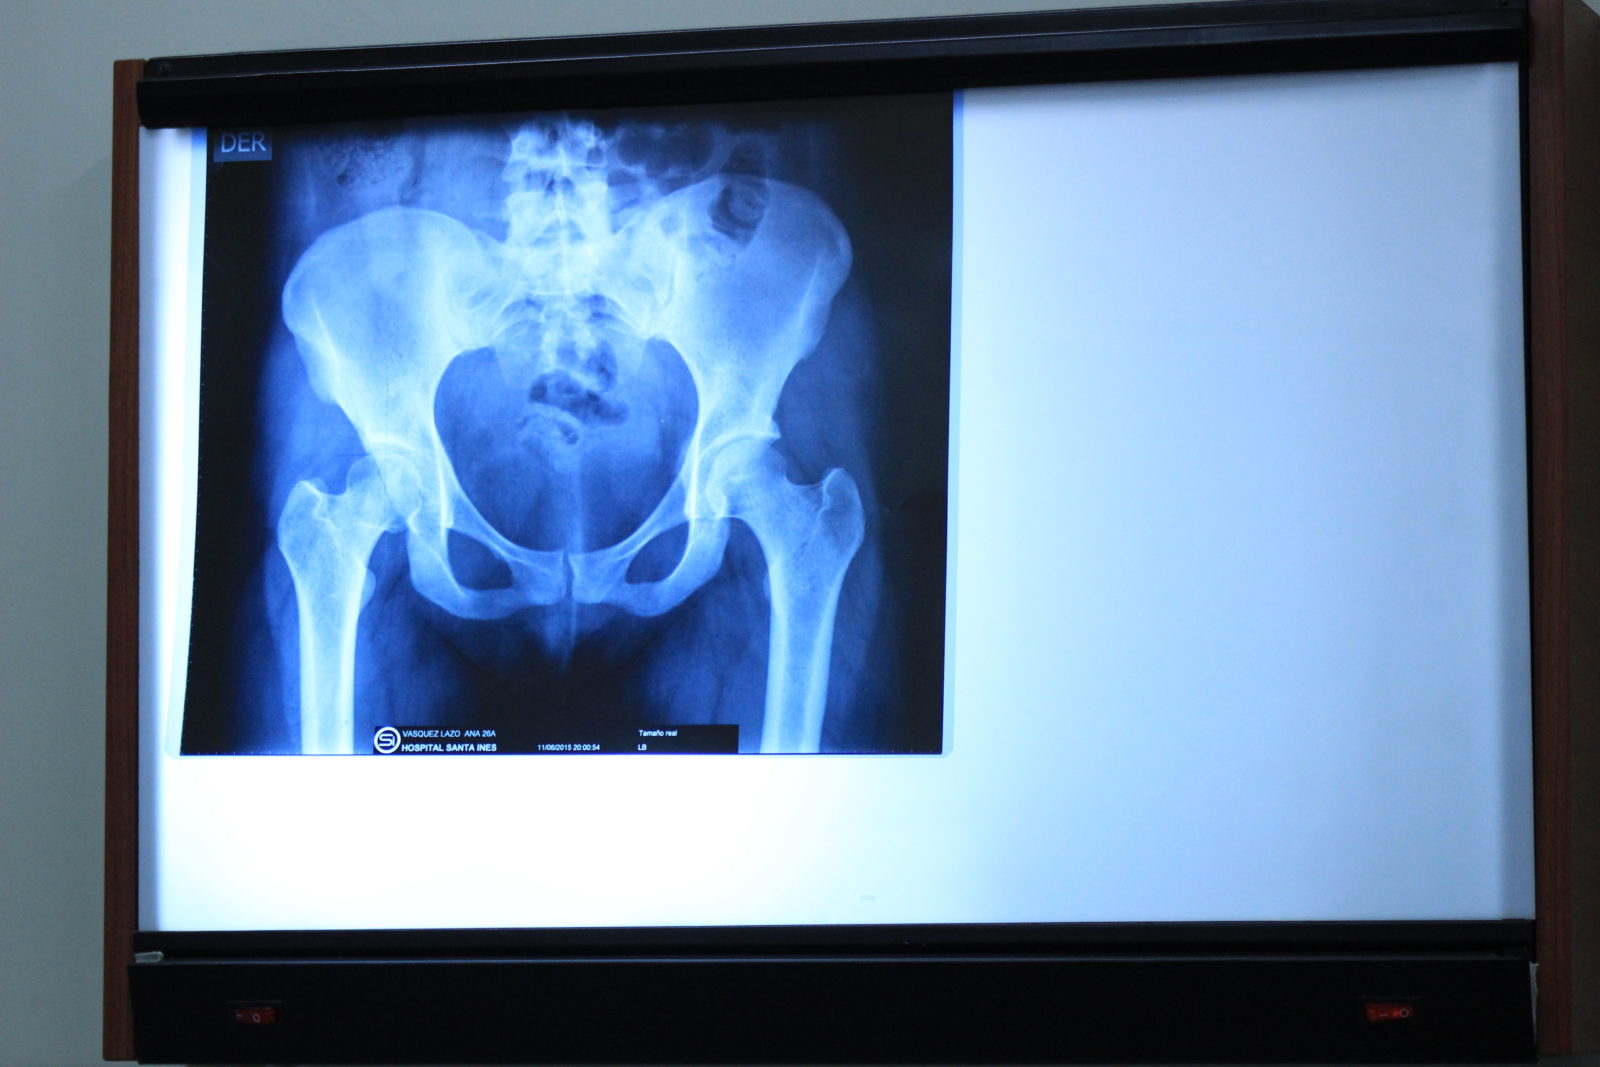

One patient scheduled for today was a young girl (we’ll call her ‘S’) who suffers from cerebral palsy in addition to hip dysplasia. S was seen in clinic last year (2015), but due to the complexities of her medical condition, the True North surgeons felt most comfortable consulting with other specialists at home in Calgary before moving forward with her case. The mission team was excited to see her return to this year’s mission clinic for care and was able to schedule her for surgery.

She was accompanied to the clinic and the hospital by her sister (C), who shared their unique and touching story with us. The sisters, abandoned by their parents at a young age, live very meagrely here in Cuenca with the C’s infant son. Supported by very little income, earned by C through the sale of fruit or goods on street corners, they don’t always have food for everyone to eat. Usually, C goes without when there isn’t enough to go around. With S’s serious physical limitations, the family has an added obstacle: it’s difficult to move quickly when the street becomes dangerous or when the authorities show up to evict them. Given her condition, S needs a caregiver and C says she is more than happy to provide for both her sister and son- she loves them both very much. But it is difficult to manage and she knows her sister suffers daily. This surgery will not only relieve some of S’s pain, stress and immobility, but, says C, it will bring S more confidence, allow the girls to live with a little more freedom, and will prove to the world that they are strong and capable. With tears streaming down her face, C thanked the True North Missions team from the bottom of her heart and wished God’s blessings upon each of us. This was a truly humbling moment for those listening.